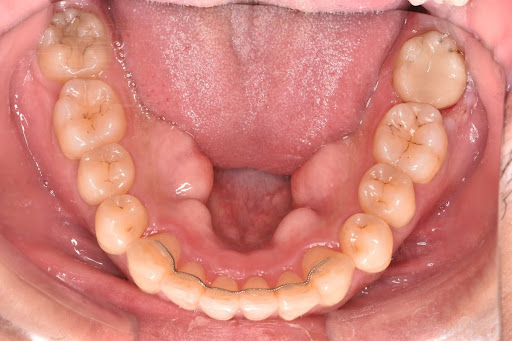

赤坂さくら歯科クリニックのインビザラインの症例写真

こちらはインビザラインのライトプランの症例写真です。